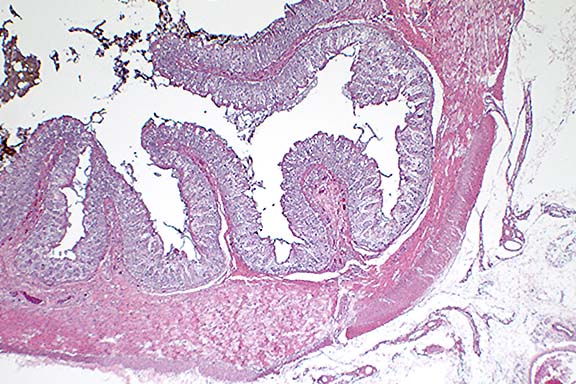

Case 23-3. Small colon. Mesenteric side showing a somewhat thin muscular layer (hypoplasia) and lack of of the submucosal and myenteric plexuses (no ganglion cells). 2X

Submitted tissues include longitudinal sections of portions of the large colons and a transverse section of the small colon. Subgross examination of sections of small colon reveal the extremely small diameter of this filly's colon. The small size may be due to hypoplasia. Within the muscularis, myenteric ganglia are severely reduced in number although occasional nerve fibers can be identified.

Conference Note: Conference participants viewed a section of colon from an age-matched foal, provided by the moderator, which highlighted the remarkable hypoplasia which was especially notable in the tunica muscularis.